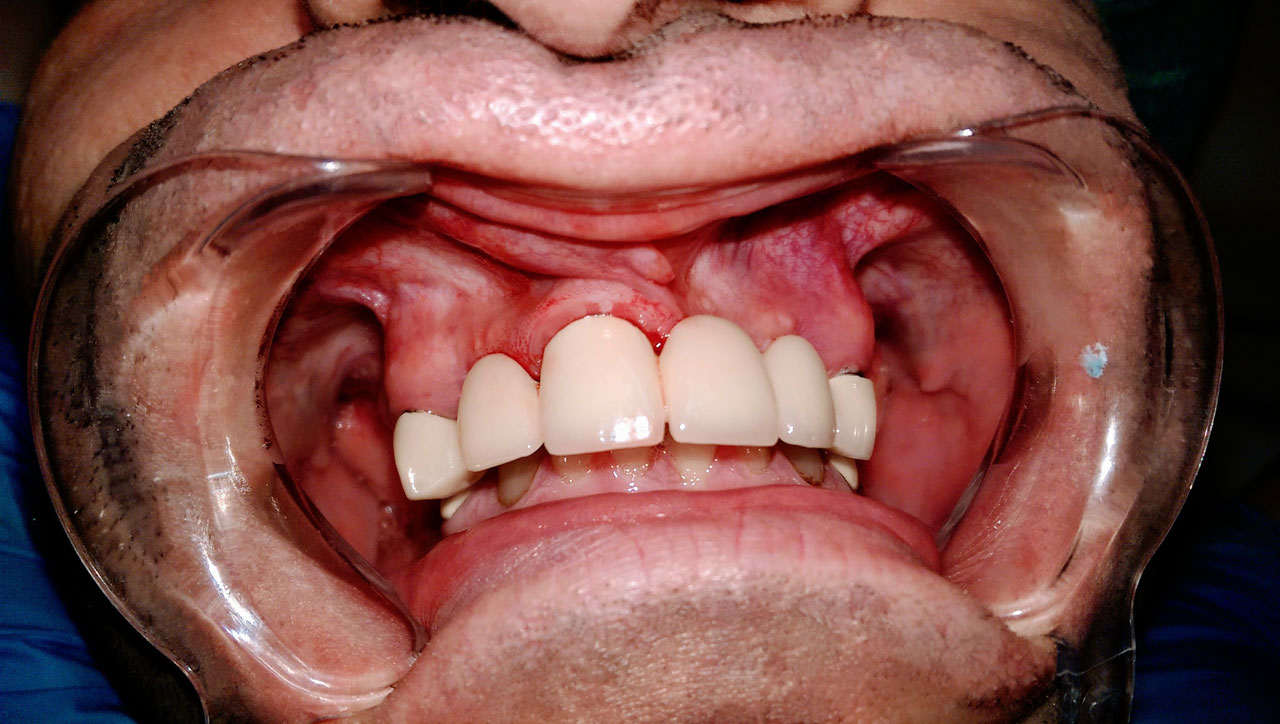

Elhanyagolt fogsor cseréje 2 nap alatt

2 nap alatt varázsoltuk ezt a szép esztétikus alsó, felső körhídat implantátumokkal megtámasztva a korábban elhanyagolt szájba. Az 1. nap 26 fogat távolítottunk el, mert annyira rossz állapotban voltak, és rögtön azonnal terhelhető IHDE svájci implantátumokat raktunk be, fentre 8, lentre 6 darabot. A sebeket összevarrtuk és intraorális szkennerrel digitális lenyomatot vettünk. 2 nap múlva pedig beragasztottuk a kész PMMA műanyag körhidakat. Dr. Kelemen Péter és a Symbion Fogtechnika munkája.